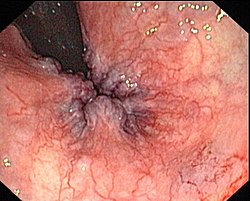

Dijagnoza hemoroida obično se postavlja fizikalnim pregledom.[10] Vizualni pregled anusa i okolnog područja dovoljan je za dijagnozu vanjskih ili prolabiranih hemoroida.[2] Rektalni pregled potreban je za otkrivanje mogućih rektalnih tumora, polipa, povećane prostate, ili apscesa.[2] Ponekad se ovaj pregled ne može provesti bez prikladne sedacije zbog bolova, iako većina unutarnjih hemoroida nije povezana s bolom.[3] Za vizualnu potvrdu unutarnjih hemoroida može biti potrebna anoskopija, koja se radi uz pomoć uređaja koji se sastoji od šuplje cijevi na čijem je kraju svjetlo.[4] Postoje dvije vrste hemoroida: vanjski i unutarnji. Oni se razlikuju po svom položaju u odnosu na lineu dentatu.[3] Neki ljudi mogu istodobno imati simptome obaju vrsta hemoroida.[4] Ako postoji bol, veća je vjerojatnost da se radi o analnoj fisuri ili vanjskim hemoroidima nego o unutarnjih hemoroidima.[4]

Unutarnji

Unutarnji hemoroidi nalaze se iznad linee dentate.[6] Pokriveni su cilindričnim epitelom u kojem nema receptora za bol.Lua error in Modul:Footnotes at line 38: data for mw.loadData contains unsupported data type 'function'. Godine 1985. unutarnji se hemoroidi klasificiraju u četiri stadija ovisno o stupnju prolapsa.[3]Lua error in Modul:Footnotes at line 38: data for mw.loadData contains unsupported data type 'function'.

- Stadij I: Nema prolapsa. Samo prominiraju krvne žile.[10]

- Stadij II: Prolaps se javlja samo u čučnju, ali se spontano smanjuje.

- Stadij III: Prolaps se javlja u čučnju, te zahtjeva manualno vraćanje.

- Stadij IV: Postoji prolaps koji se ne može manualno smanjiti.